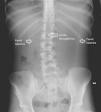

Paciente de 16 años que consultó en nuestro hospital por dolor epigástrico tras ingesta alimentaria de gran entidad realizada 8 horas antes. Refirió incapacidad para el vómito e indicó que había sido vista en otro centro donde se recomendó reposo digestivo y dieta blanda. Diagnosticada de bulimia nerviosa no restrictiva en tratamiento farmacológico (bromazepam, topiramato y fluoxetina) con control parcial de la sintomatología había presentado episodios previos semejantes pero logrando el vómito posteriormente. No asociaba otros antecedentes personales o familiares de interés. La paciente mostraba gran agitación, inquietud e indicaba dolor abdominal generalizado. En la exploración física se objetivó distensión abdominal con defensa voluntaria a la palpación. No presentaba alteraciones en la frecuencia cardiaca o tensión arterial con bioquímica sanguínea y gasometría venosa normales (ph 7,37 con ácido láctico de 0,5mmol/l). Ante la sospecha de dilatación gástrica se decidió introducir una sonda por vía nasogástrica extrayéndose 700ml de contenido estomacal. Posteriormente se solicitó una radiografía de abdomen que demostró una gran dilatación gástrica con el límite inferior del estómago en la región pélvica (fig. 1). Se decidió ingreso en la unidad de cuidados intensivos, para observación continua, ante el riesgo de rotura gástrica. Se mantuvo a dieta absoluta durante 48h y recibió fluidoterapia según necesidades basales. Se inició tratamiento procinético y protector de la mucosa estomacal. Durante su permanencia en la UCI se mantuvo la sonda nasogástrica abierta para continuar el vaciamiento gástrico. Tras control radiológico (fig. 2), y dada la ausencia de complicaciones, se reinició la alimentación oral progresiva sin incidencias. Posteriormente, recibió el alta bajo control de servicio de psiquiatría.

El diagnóstico de imagen se fundamenta en la radiografía de abdomen permitiendo esta una valoración aproximada de la dilatación gástrica. En aquellos casos en los que no existan antecedentes de pérdida de peso, enlentecimiento del vaciado gástrico, atracones alimenticios o fenómenos obstructivos conocidos puede ser necesaria la realización de una tomografía computarizada abdominal con el objeto de descartar anomalías anatómicas o procesos intercurrentes desencadenantes de DGA1.